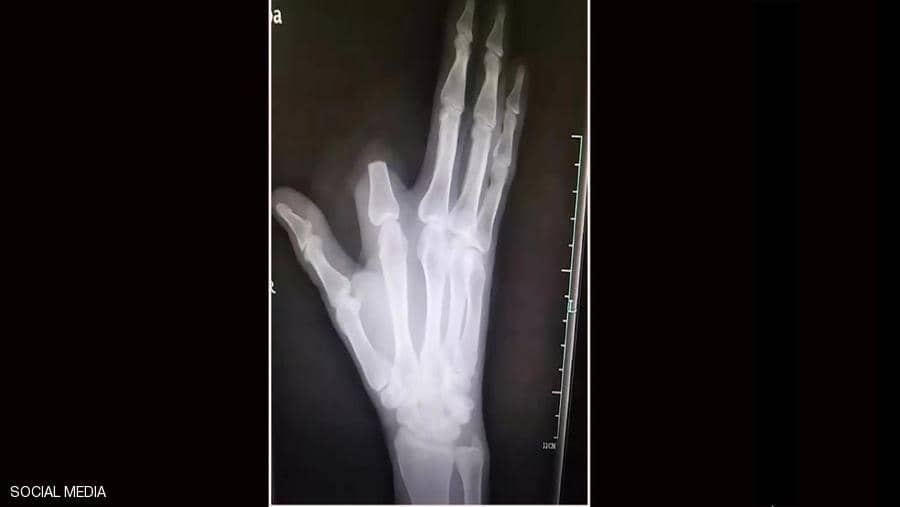

وظن الرجل أن لدغة الأفعى شديدة السمية وقد تؤدي إلى موته فورا، فسارع إلى قطع إصبعه بسكين كان بحوزته من أجل “إنقاذ حياته”، بحسب ما أوردت شبكة “فوكس نيوز”.